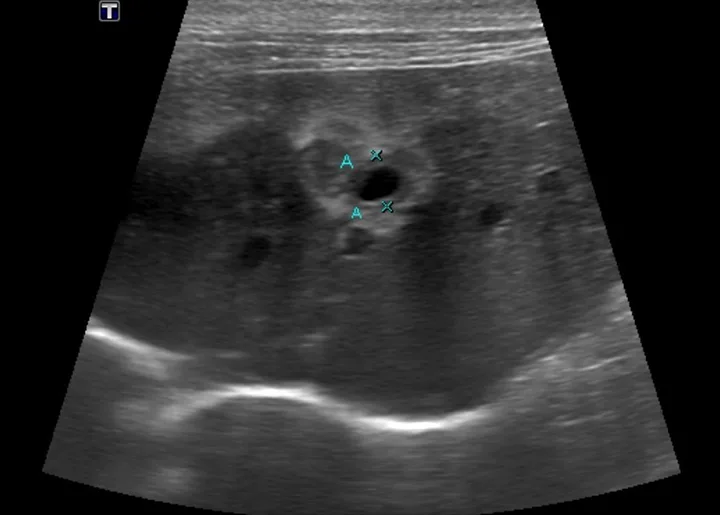

Abdominal ultrasonography is increasingly important for diagnosing pancreatitis via identification of pancreatic enlargement, changes in echogenicity, free fluid surrounding the pancreas, and hyperechogenicity of peripancreatic fat (Figures 1 and 2). Results of a study demonstrated good correlation with fPLI elevations.16

Ultrasound image of liver in a cat with markers denoting walls of the common bile duct.

FIGURE 2

Ultrasound of the liver and common bile duct in a cat with acute pancreatitis and triaditis. Hypoechogenicity of the liver and an enlarged common bile duct (As; 5 mm measured by Xs) with thickened walls are visible.